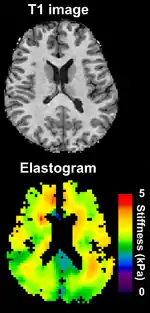

Magnetic resonance elastography (MRE)

Magnetic resonance elastography (MRE)[26] was introduced in the mid-1990s, and multiple clinical applications have been investigated. In MRE, a mechanical vibrator is used on the surface of the patient's body; this creates shear waves that travel into the patient's deeper tissues. An imaging acquisition sequence that measures the velocity of the waves is used, and this is used to infer the tissue's stiffness (the shear modulus).[27][28] The result of an MRE scan is a quantitative 3-D map of the tissue stiffness, as well as a conventional 3-D MRI image.

One strength of MRE is the resulting 3-D elasticity map, which can cover an entire organ.[2] Because MRI is not limited by air or bone, it can access some tissues ultrasound cannot, notably the brain. It also has the advantage of being more uniform across operators and less dependent on operator skill than most methods of ultrasound elastography.

MR elastography has made significant advances over the past few years with acquisition times down to a minute or less and has been used in a variety of medical applications including cardiology research on living human hearts. MR elastography's short acquisition time also makes it competitive with other elastography techniques.

Because elastography does not have the same limitations as manual palpation, it is being investigated in some areas for which there is no history of diagnosis with manual palpation. For example, magnetic resonance elastography is capable of assessing the stiffness of the brain,[29] and there is a growing body of scientific literature on elastography in healthy and diseased brains.